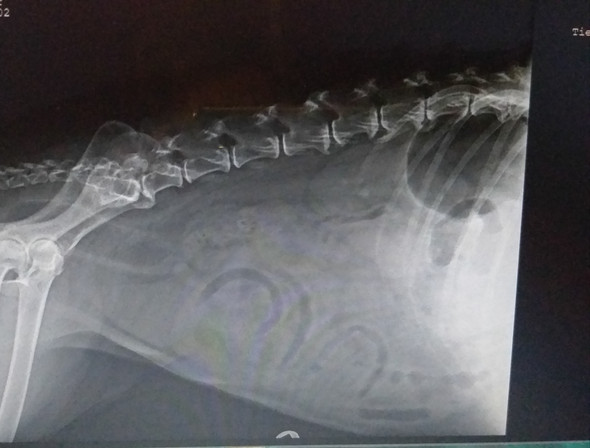

SechsKiloTumor Kann dieser Hund noch gerettet werden?

Dieser Hund hatte einen 6 kg schweren Tumor... Eine Tierschutzverein